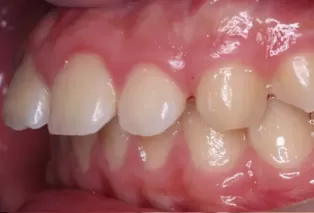

Intraoral photos